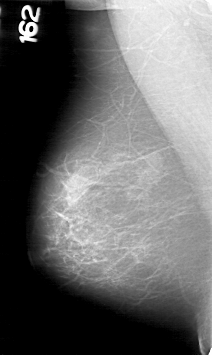

D_4039_1.LEFT_MLO

RIGHT_CC LINES 5281 PIXELS_PER_LINE 2821 BITS_PER_PIXEL 12 RESOLUTION 43.5 NON_OVERLAY

RIGHT_MLO LINES 5311 PIXELS_PER_LINE 3166 BITS_PER_PIXEL 12 RESOLUTION 43.5 NON_OVERLAY